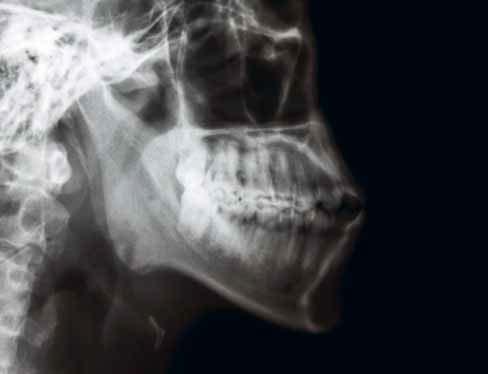

1 stříška kloubní jamky čelistního kloubu

2 articulatio temporomandibularis (čelistní kloub)

3 caput mandibulae (hlavice dolní čelisti)

4 sinus maxillaris (dutina horní čelisti)

5 cavitas nasi (nosní dutina)

6 processus coronoideus (krkavčitý výběžek)

7 maxilla (horní čelist)

8 ramus mandibulae (rameno dolní čelisti)

9 angulus mandibulae (úhel dolní čelisti)

10 dentes molares (stoličky)

11 canalis mandibulae (kanál v dolní čelisti)

12 dentes premolares (premoláry)

13 dens caninus (špičák)

14 dentes incisivi (řezáky)

15 foramen mentale

16 tuberculum mentale (sumace s projasněním trachey)

19 canalis radicis dentis (kořenový kanál)

20 cavitas dentis (pulparis) (dřeňová dutina zubu)

21 dentin korunky (zubovina)

22 sklovina 23 foramen mentale

24 radix dentis (zubní kořen)

25 dentes incisivi (řezáky)

26 dens caninus (špičák)

27 dentes premolares (premoláry)

28 dentes molares (stoličky)

10 recessus alveolaris (dno dutiny horní čelisti) 11 sinus maxillaris (dutina horní čelisti) 12 fossa pterygopalatina 13 processus pterygoideus (křídlový výběžek kosti klínové) 14 angulus mandibulae (úhel dolní čelisti) 15 stín jazyka 16 canalis mandibulae (kanál v dolní čelisti) 17 os hyoideum (jazylka) 18 foramen apicis radicis dentis